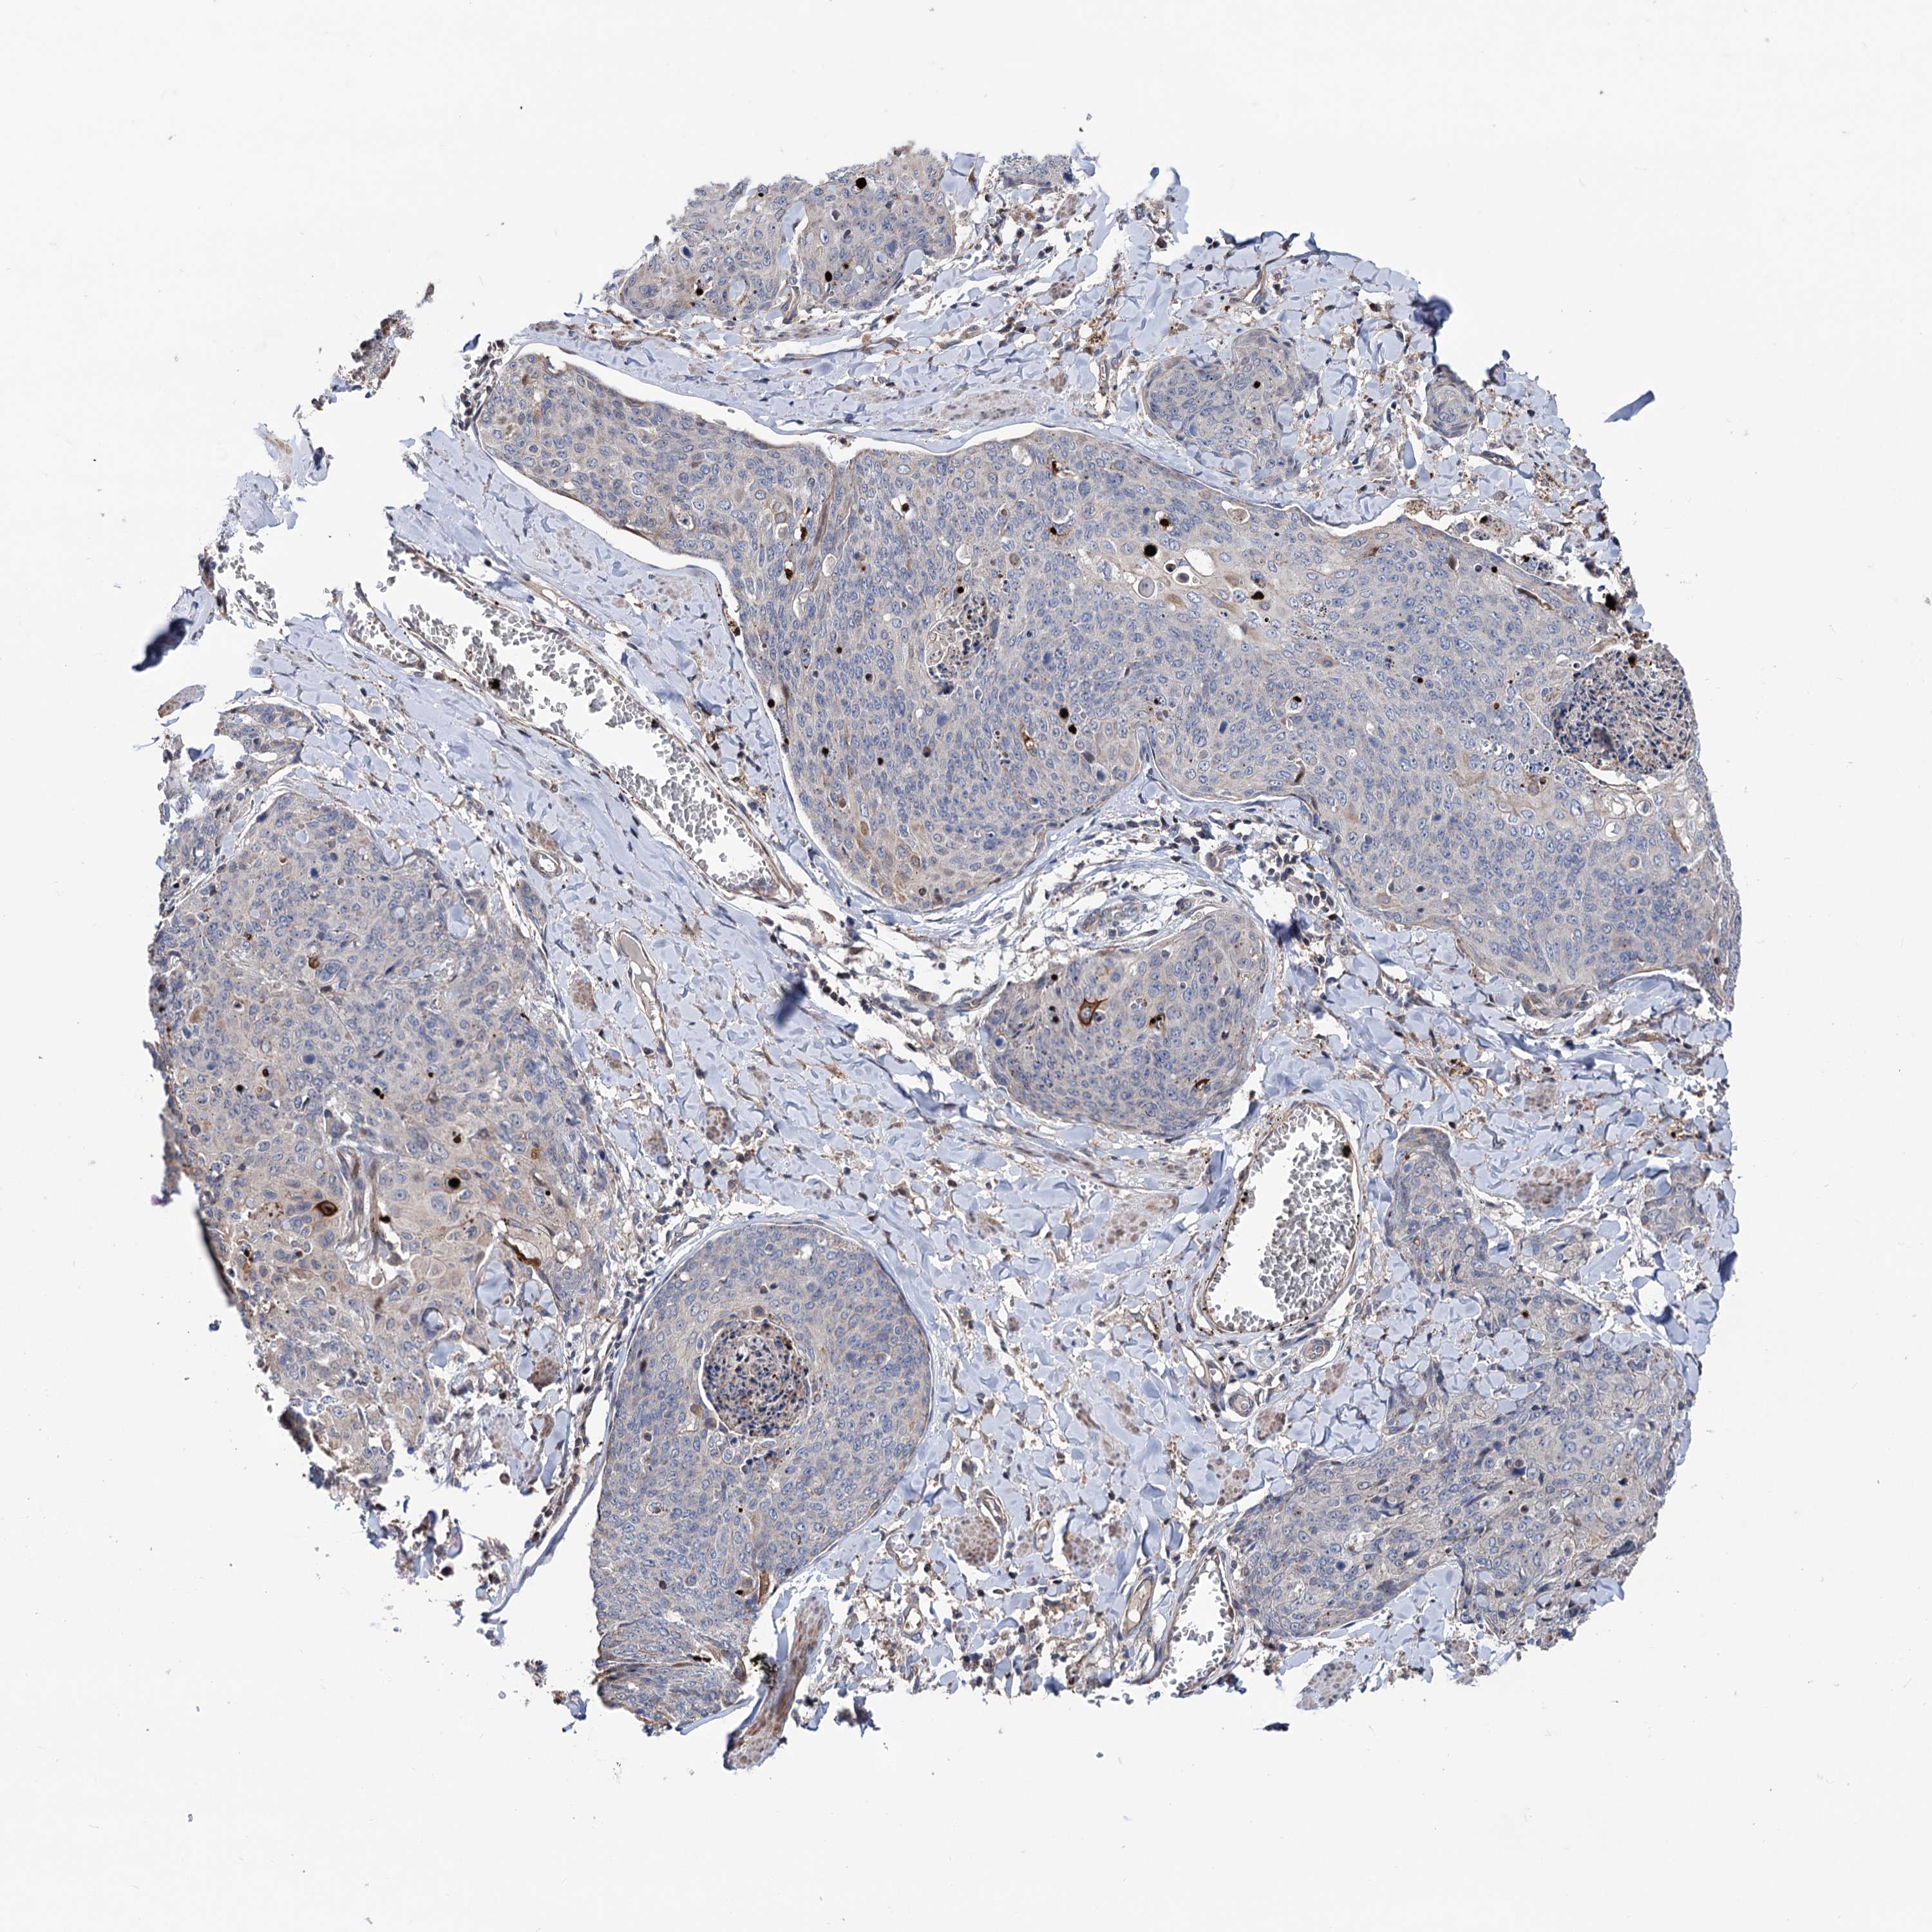

SKIN CANCER - Protein expressioni

A mouse-over function shows sample information and annotation data. Click on an image to view it in a full screen mode. Samples can be filtered based on level of antibody staining by selecting one or several of the following categories: high, medium, low and not detected. The assay and annotation is described here.

Antibody stainingi

Antibody staining in the annotated cell types in the current human tissue is reported as not detected, low, medium, or high, based on conventional immunohistochemistry profiling in selected tissues. This score is based on the combination of the staining intensity and fraction of stained cells.

Each image is clickable and will lead to virtual microscopy that enables deeper exploration of all samples and also displays staining intensity scores, fraction scores and subcellular localization as well as patient and tissue information for each sample.

Antibody HPA038838

Basal cell carcinoma